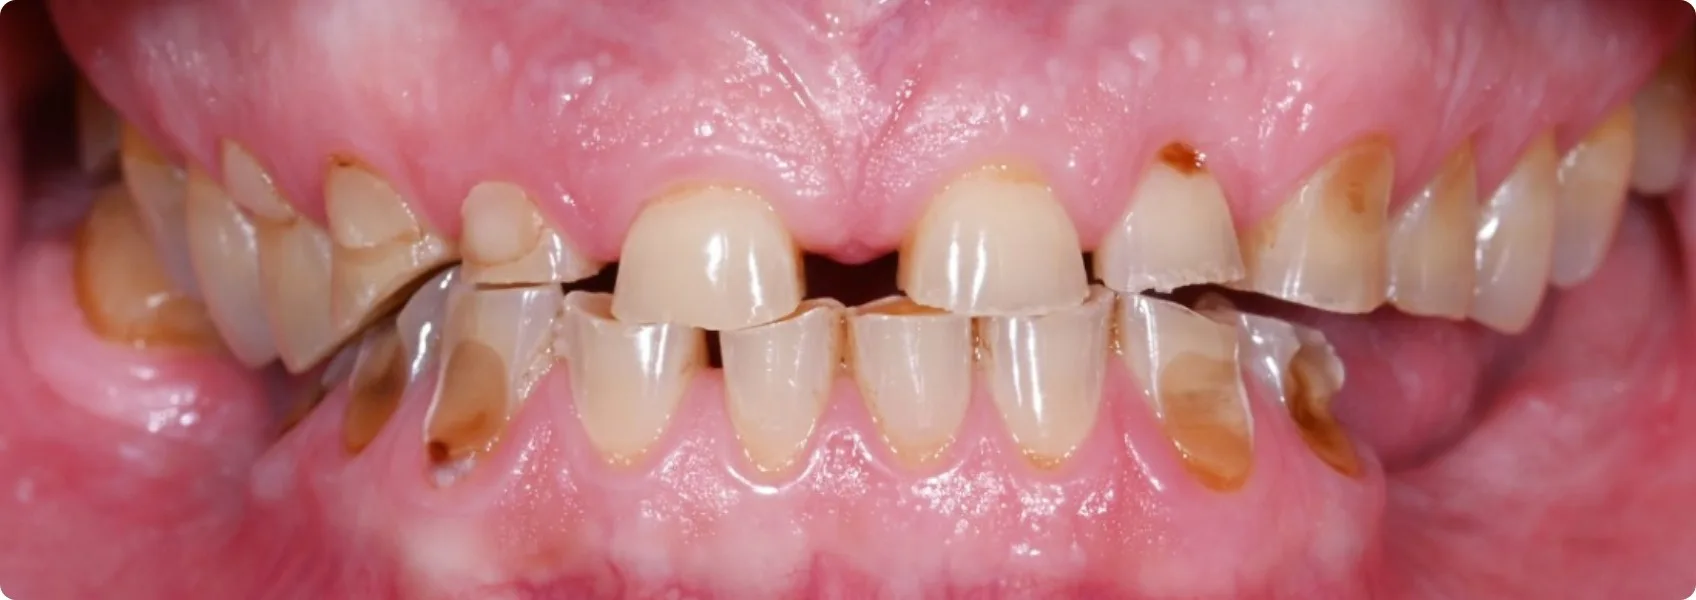

Pacjent trafił do nas z mocno zaburzonym zgryzem — i bólem.

Zęby były nie tylko bardzo mocno starte, ale brakowało też wielu z nich w dolnym łuku. Relacja między górnymi a dolnymi zębami była tak zaburzona, że Pacjent de facto nie posiadał prawidłowego zgryzu!

To rodziło codzienne trudności: problemy z gryzieniem, żuciem, a nawet mówieniem. Dodatkowo potęgował się ból w stawie skroniowo-żuchwowym. Lek. dent. Adrian Złotogórski zakwalifikował Pacjenta do pełnej rekonstrukcji zgryzu. To była jedyna droga do odzyskania komfortu i funkcji.

Kiedy implanty się goją, pora na naprawę funkcji. Znajdujemy prawidłowy zgryz… choć nie jest to proste.

Jednym z największych wyzwań było odnalezienie prawidłowej, terapeutycznej pozycji żuchwy względem szczęki. Bez tego cała rekonstrukcja byłaby obarczona ryzykiem niepowodzenia.

Starte i brakujące zęby nie dawały naturalnych wskazówek, jaka powinna być prawidłowa pozycja żuchwy (dolnych zębów) względem szczęki (górnych). Mięśnie żucia działały według utrwalonych, złych nawyków. Trudność polegała na określeniu fizjologicznej, komfortowej pozycji żuchwy wbrew temu oporowi mięśni.

Wykonanie kosztownej odbudowy protetycznej w złej pozycji oznaczałoby jej szybkie zniszczenie. Praca pękłaby lub obluzowała się prac, nasilając bóle stawów. Cały sukces leczenia zależał od tej prawidłowej podstawy.